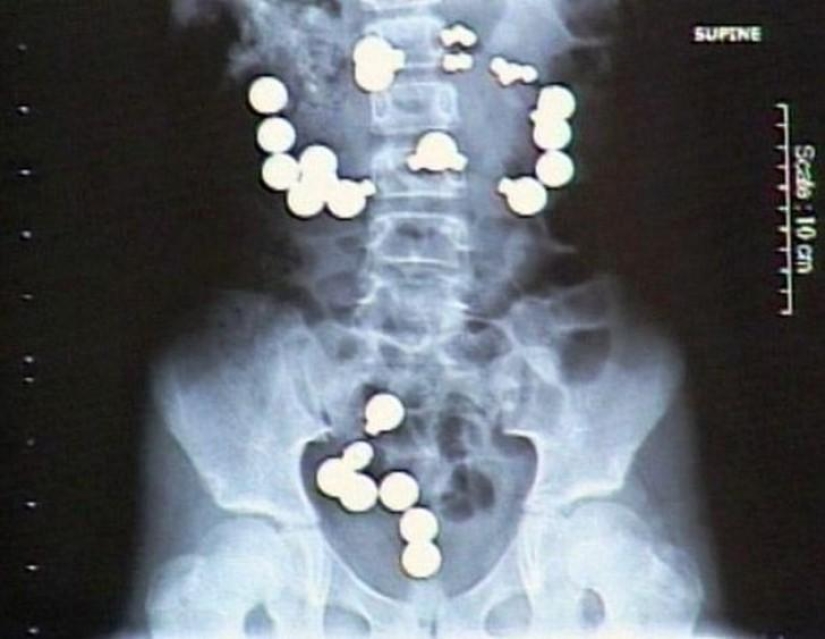

Magnets.